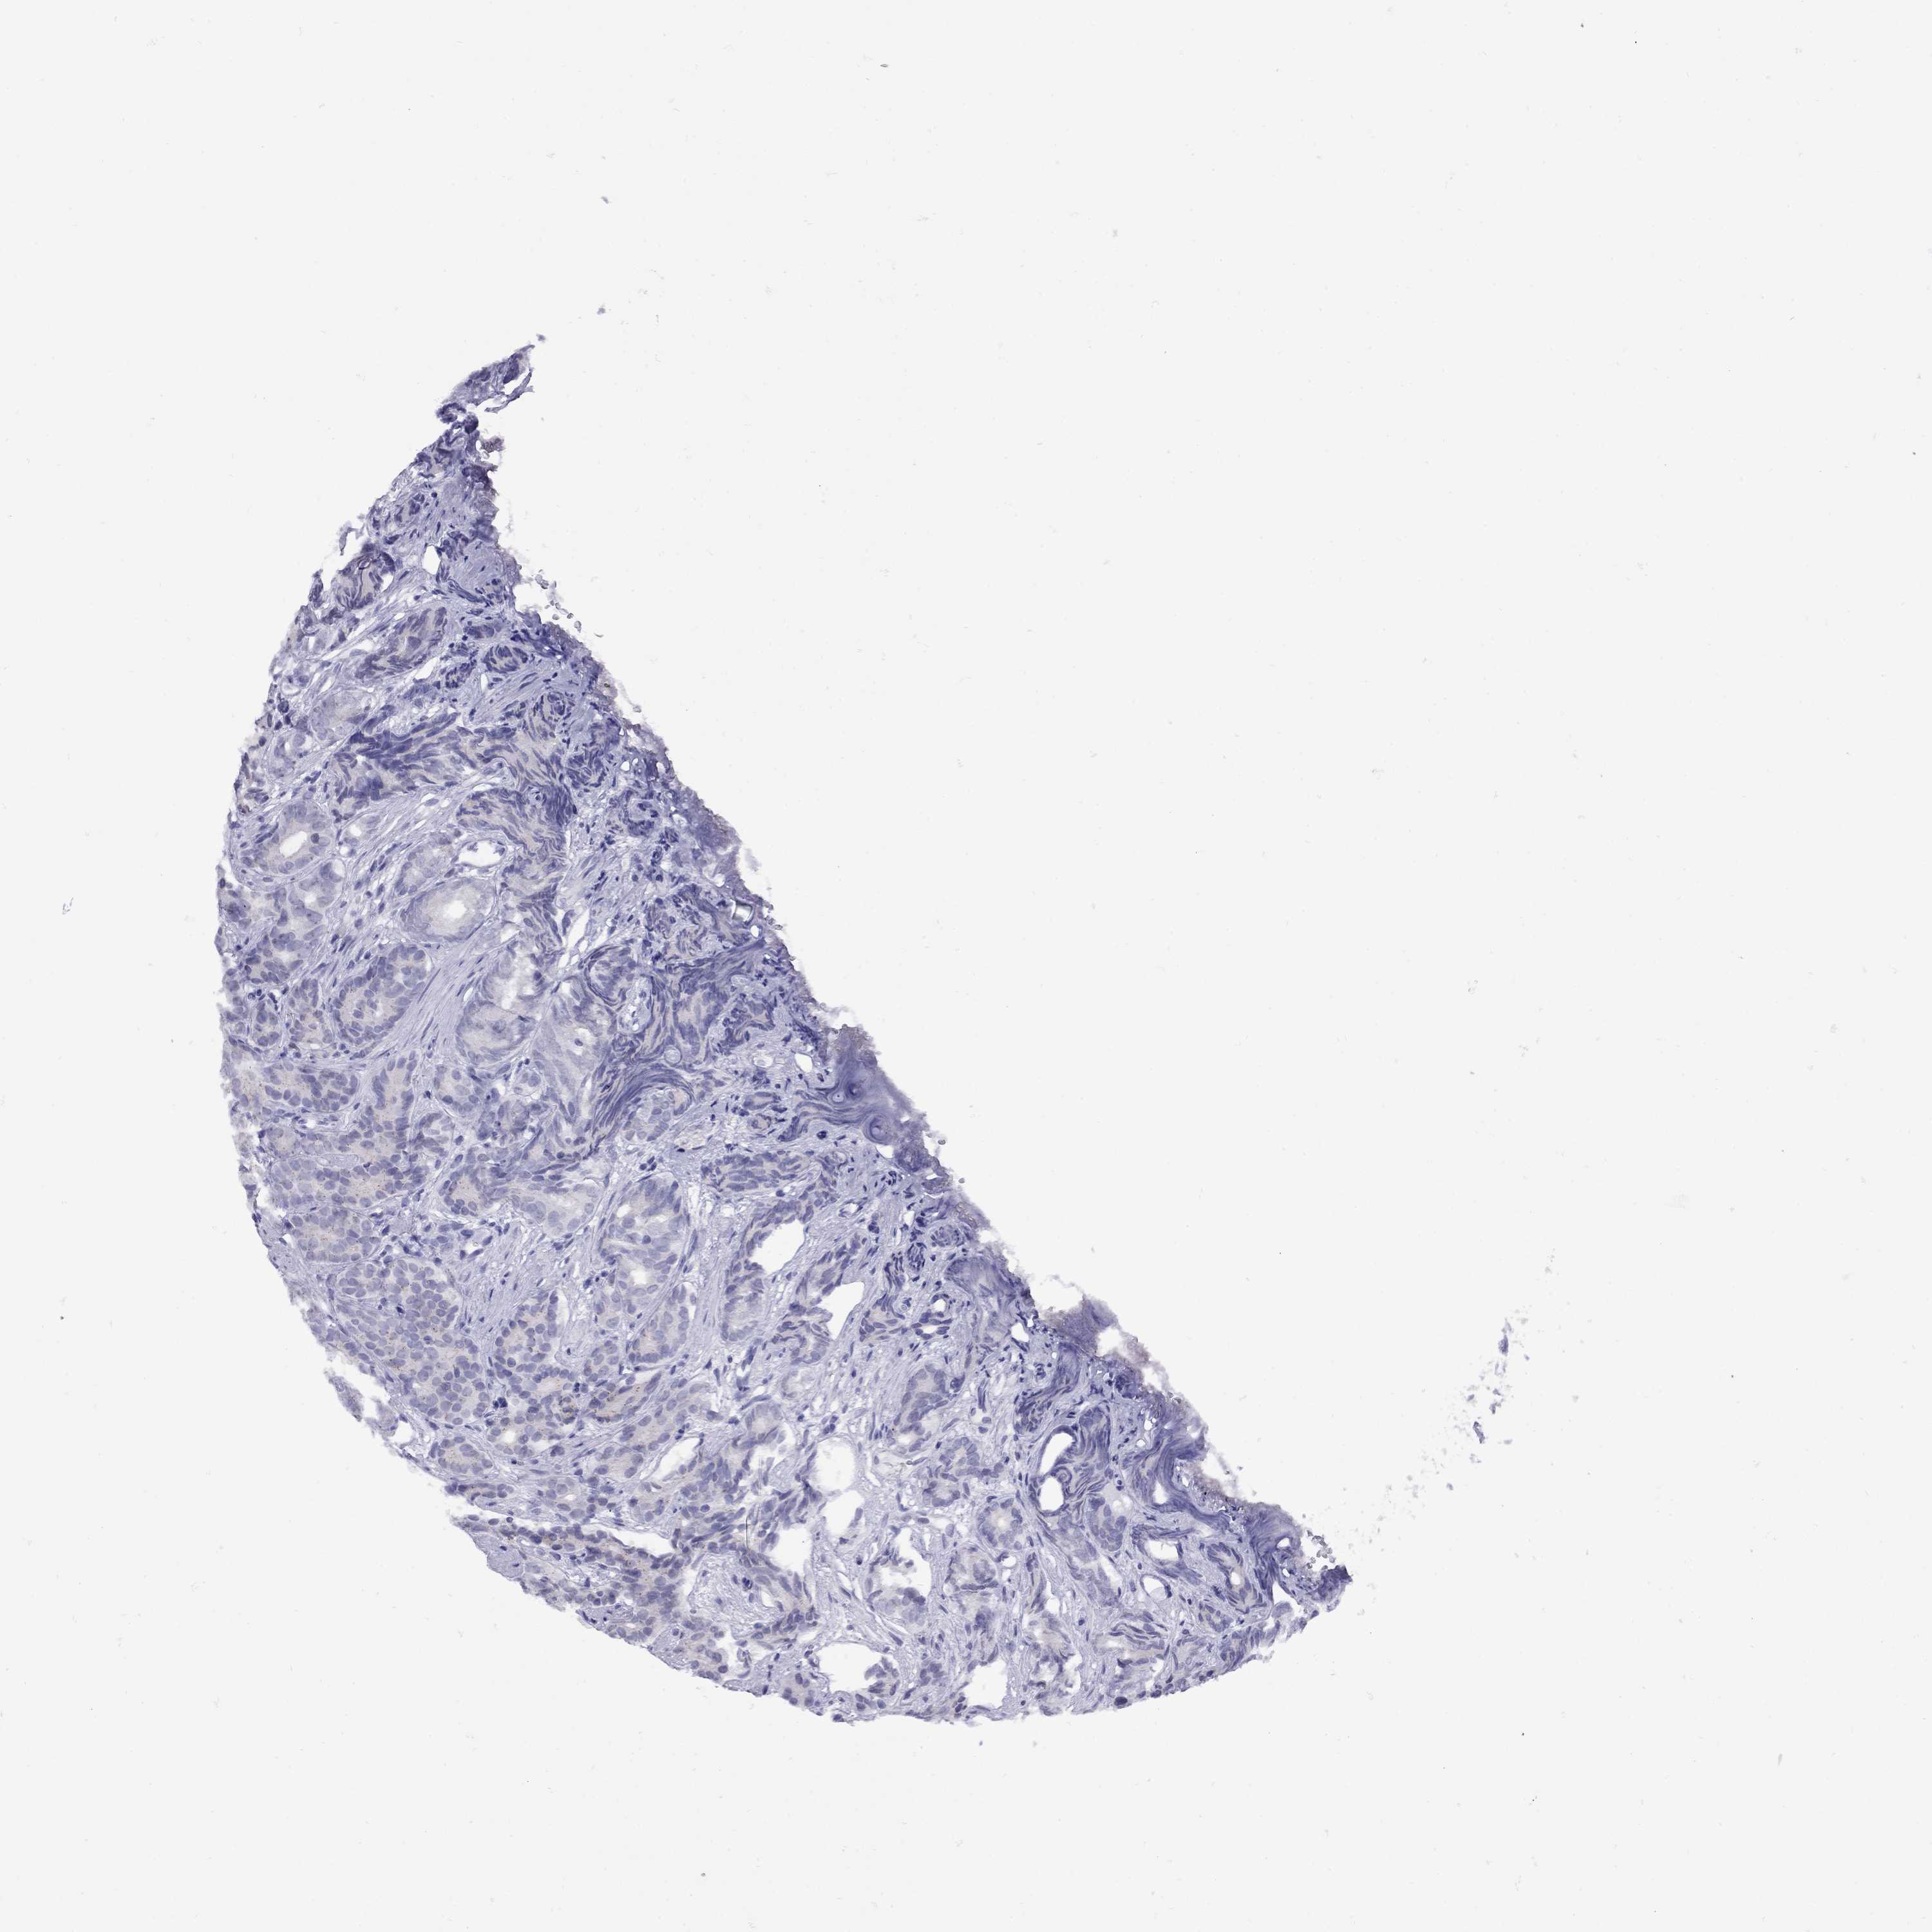

PROSTATE CANCER - Protein expressioni

A mouse-over function shows sample information and annotation data. Click on an image to view it in a full screen mode. Samples can be filtered based on level of antibody staining by selecting one or several of the following categories: high, medium, low and not detected. The assay and annotation is described here.

Antibody stainingi

Antibody staining in the annotated cell types in the current human tissue is reported as not detected, low, medium, or high, based on conventional immunohistochemistry profiling in selected tissues. This score is based on the combination of the staining intensity and fraction of stained cells.

Each image is clickable and will lead to virtual microscopy that enables deeper exploration of all samples and also displays staining intensity scores, fraction scores and subcellular localization as well as patient and tissue information for each sample.

Antibody HPA035881

Staining

High

Medium

Low

Not detected

Intensity

Strong

Moderate

Weak

Negative

Quantity

>75%

75%-25%

<25%

None

Location

Nuclear

Cytoplasmic/membranous

Cytoplasmic/membranous,nuclear

Adenocarcinoma, Medium grade

Adenocarcinoma, High grade

Adenocarcinoma, NOS

Adenocarcinoma, Low grade